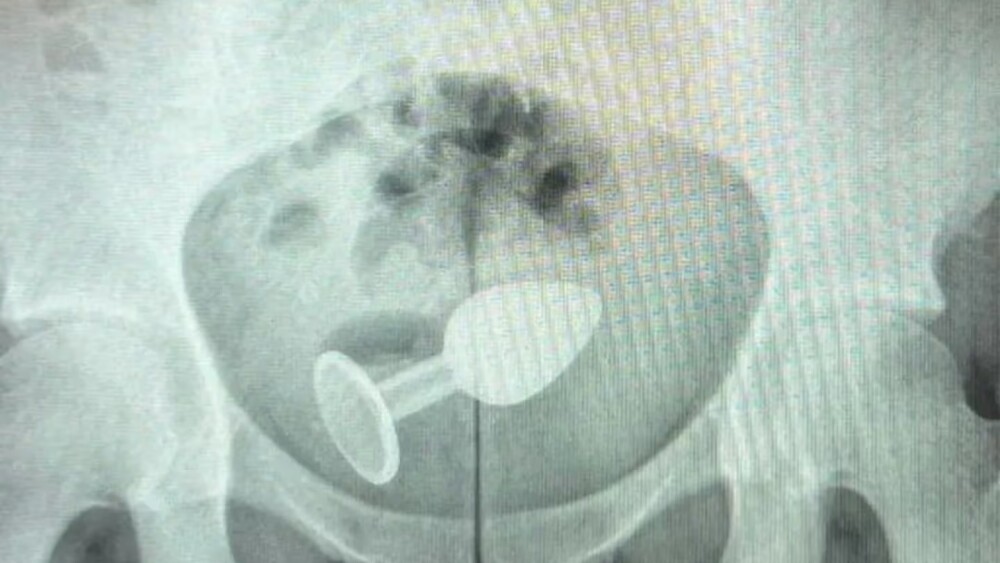

La mujer, habitante de Brasil, tuvo que ir al hospital de emergencia, donde la atendió un ciujano coloproctólogo de nombre Daniel Brosco. Le realizaron una radiografía, y ahí estaba… Se trataba de un plug anal, que se quedó incrustado en su colon.